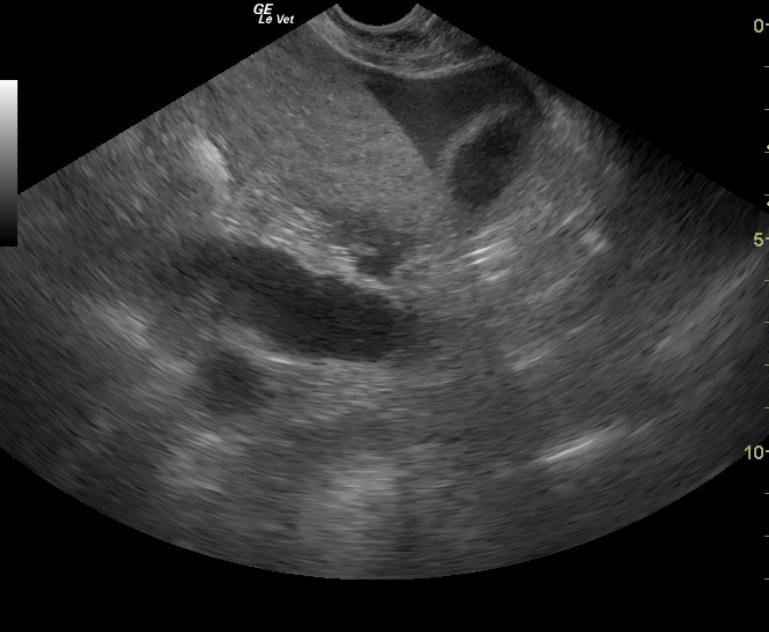

An 11-year-old FS DSH with history of asthma was presented for acute hind leg paresis. Abnormalities on physical examination were tachycardic, pronounced gallop rhythm, absent femoral pulses, all four extremities were cool, and she was unable to stand. The patient was treated with Lasix, nitroglycerin, and heparin. Within a few hours she was able to ambulate on her own but was knuckling over on all fours